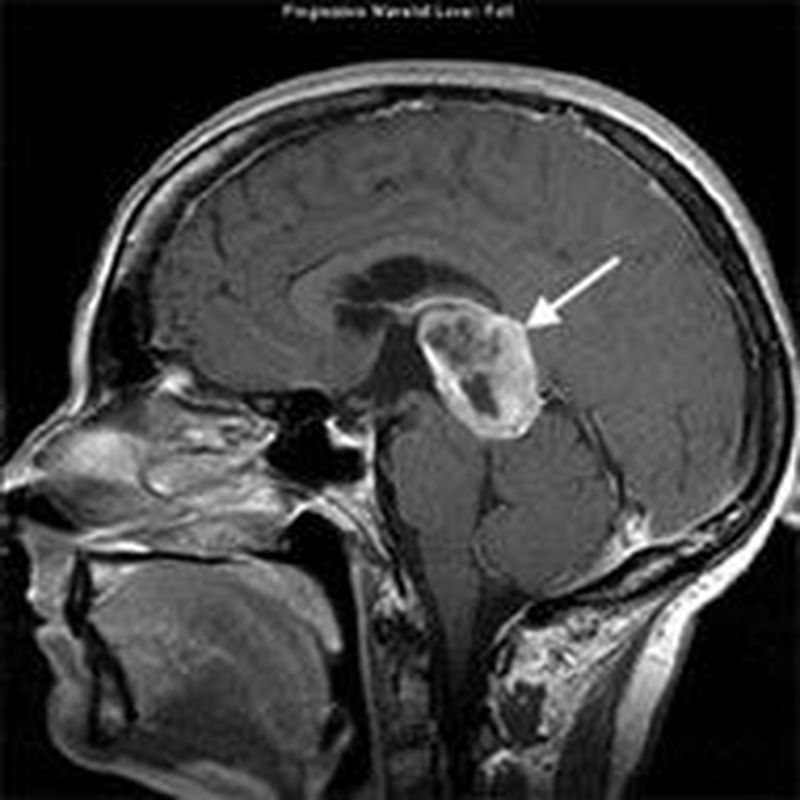

Pineal glands tumours are a diverse group of neoplasms. The most common is a germ cell tumour, which arises from residual embryonic tissue in the gland. It presents with the classical symptoms of a space occupying lesion – headache, nausea and vomiting. The tumour can also cause Parinaud syndrome – inability to move the eyes upwards – this is due to compression of the superior colliculi. In addition, obstruction of the cerebral aqueduct may produce hydrocephalus. In children, a pineal gland tumour (which invades and destroys the gland), produces an accelerated onset of puberty. Thus, it is thought that one of the functions of the gland is to inhibit sexual development.